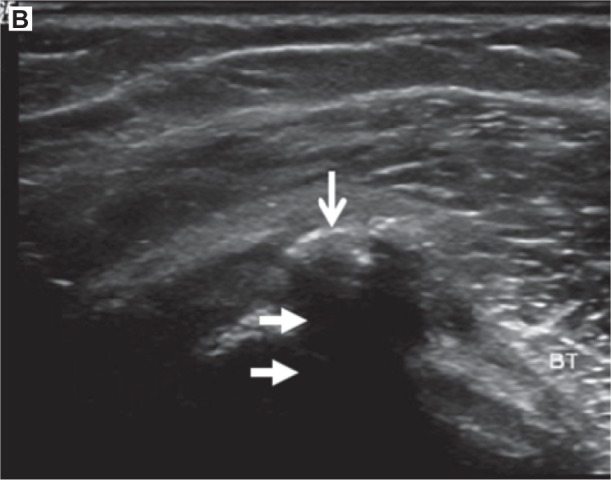

Sombra acústica

La sombra acústica es ese “vacío” oscuro que aparece por debajo de una estructura que bloquea el haz. Se ve como una zona hipoecoica o negra porque el sonido no llega con suficiente energía a lo que hay detrás.

Suele aparecer cuando el tejido atenúa mucho el ultrasonido o cuando actúa como un reflector muy potente. Por eso es típica bajo la cortical ósea y también bajo calcificaciones.

A continuación, te ponemos 2 ejemplos prácticos extraídos del artículo de Chingkoe et al (referencia 1 de la bibliografía de este artículo):

A nivel clínico tiene una doble cara. Cuando ves un foco hiperecogénico con una sombra por debajo, suele indicar una estructura dura (hueso o calcificación) y eso orienta. El problema es que esa misma sombra puede ocultar el tejido que hay debajo. Por ejemplo, una calcificación puede dificultar la visualización del tendón profundo y hacer que una rotura parcial pase desapercibida.

La forma práctica de reducir errores, a menudo consiste en inclinar ligeramente la sonda y buscar otra trayectoria del haz que “bordee” el obstáculo. Si además ajustas el foco a la profundidad real del objetivo y confirmas la imagen en dos planos, minimizas muchísimo el riesgo de confundir una sombra con un defecto real del tejido.